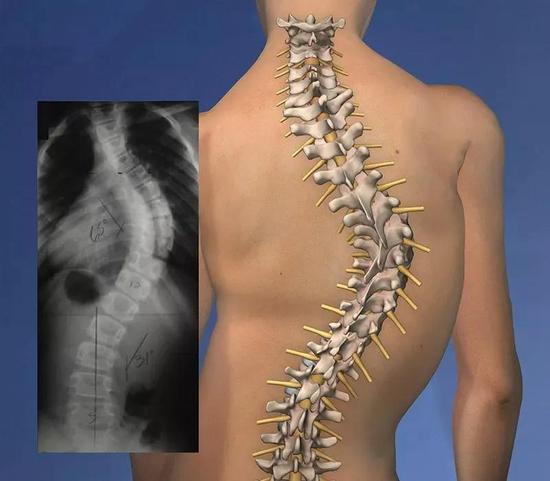

什么是脊柱侧弯

脊椎侧弯是一种常见的骨骼问题。

在站姿下,不管从正面或背面看,正常的脊椎排列应该是身体左右两边对称,并且正常的脊椎排列从上到下是呈一直线的。

如果在站姿下看到脊椎向身体的任何一边弯曲歪斜,就是有可能是脊椎侧弯,左右手臂与躯干之间的空隙不对称,右侧肩膀较高。

然而大部分的脊椎侧弯并不只有单一平面的左右倾斜,通常会伴随着脊椎旋转,往往也会影响到肩胛骨的动作,导致肩关节的活动度受限。

首先你需要确定你的脊柱侧弯程度到底有多严重,根据不同的严重程度有不同的矫正方法。

严重

如果侧弯超过了40°,这就是属于严重的脊柱侧弯,就要考虑是否要进行矫正手术了。切开皮肤后置入钢钉和矫正器…

中度

20~40°的侧弯,属于中度的脊柱侧弯,我们可以通过一些康复训练进行治疗,同时需要使用支具进行治疗。

轻度